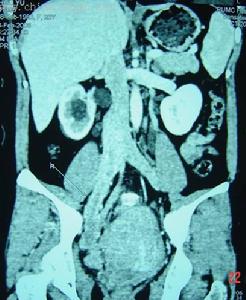

2.根據病情,臨床表現、症狀體徵選擇做心電圖、X線、B超等檢查。